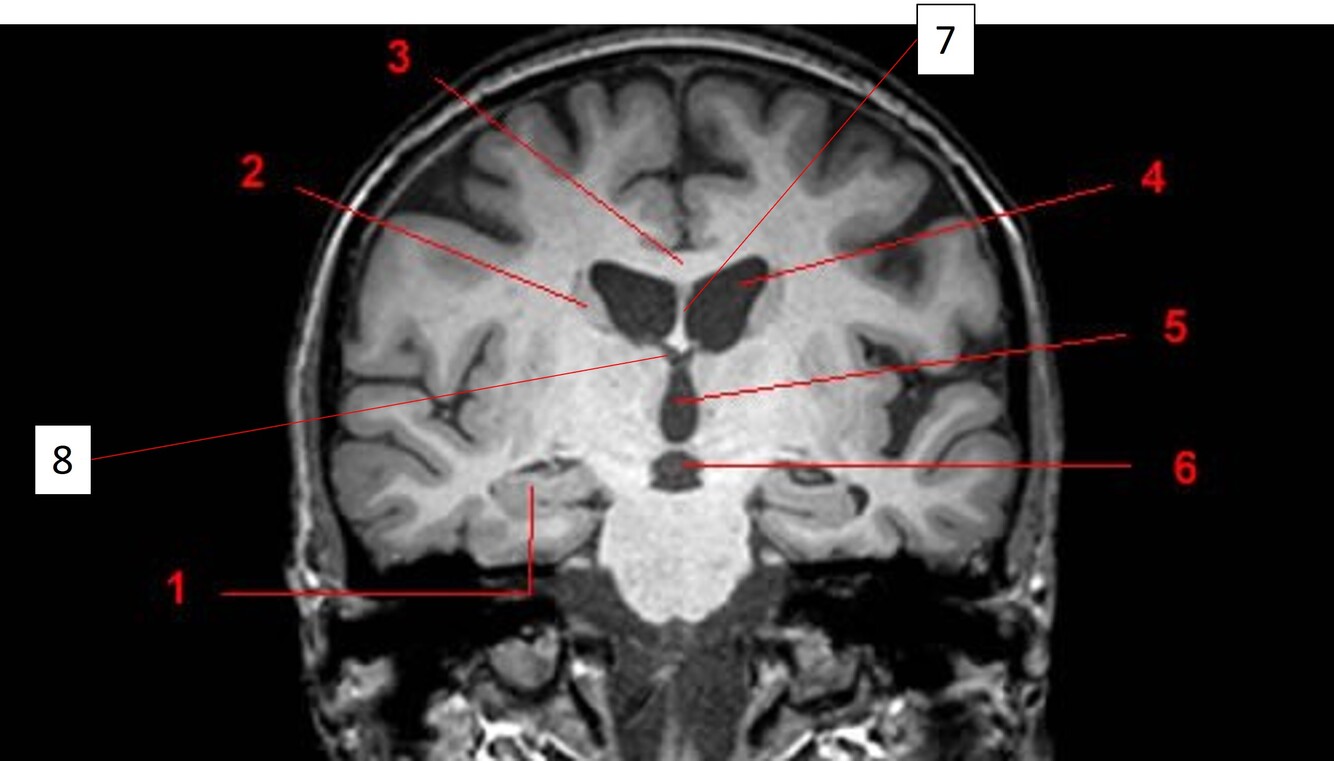

Label 2,3,4,5,7,8

2=Rt Caudate nucleus

3=Corpus callosum

4=Lt lateral ventricle

5=Third ventricle

7= Septum Pellucidum

8= Rt Interventricular foramen